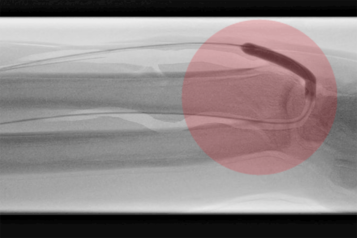

3. Stentimplantation – Einsetzen eines Stentes/ Gefäßstütze

Nach der Gefäßweitung kann durch Einrisse in den inneren Ablagerungen oder durch die Elastizität der Gefäßwand die Weitung nur ungenügend erfolgreich sein. Zur Stabilisierung des Befundes wird dann in diese Gefäßregion ein Stent eingesetzt. Dieser besteht aus einem feinen starren oder flexiblen Edelmetallgeflecht und kann auch mit Medikamenten gegen die Arteriosklerose oder zur Verhinderung der Bildung von Blutgerinnseln beschichtet sein.

Unter bestimmten Bedingungen, v.a. bei Verletzungen der Gefäße mit daraus resultierender Blutung oder lokalen Gefäßerweiterungen, werden Stents mit einer Ummantelung eingesetzt, die die Gefäßwand abdichten oder die Erweiterung überbrücken.